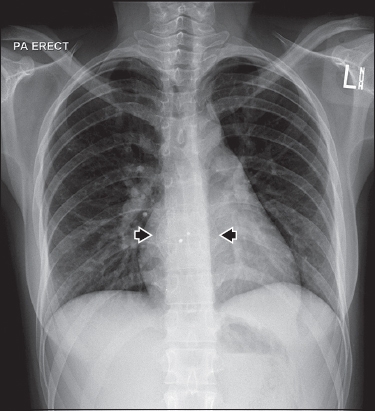

Chest radiography (

Fig. 1

Frontal chest radiograph.

Anterior-posterior chest radiograph (